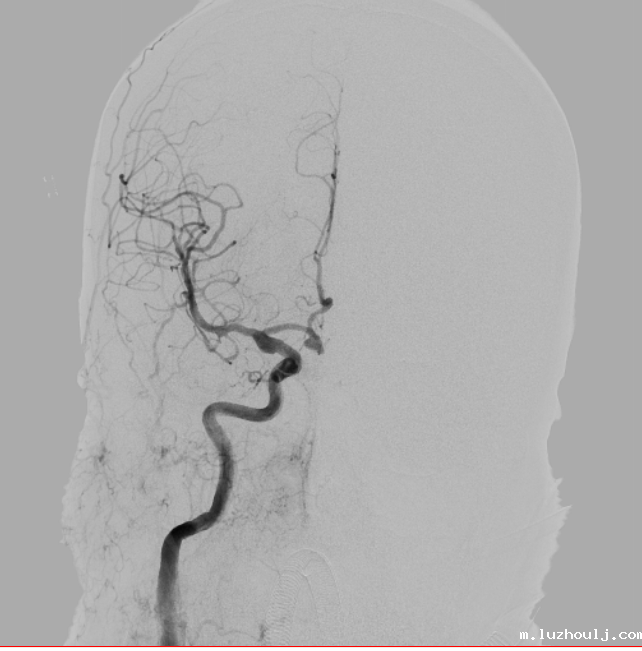

DSA显示颅内动脉瘤形态不规则、有分叶